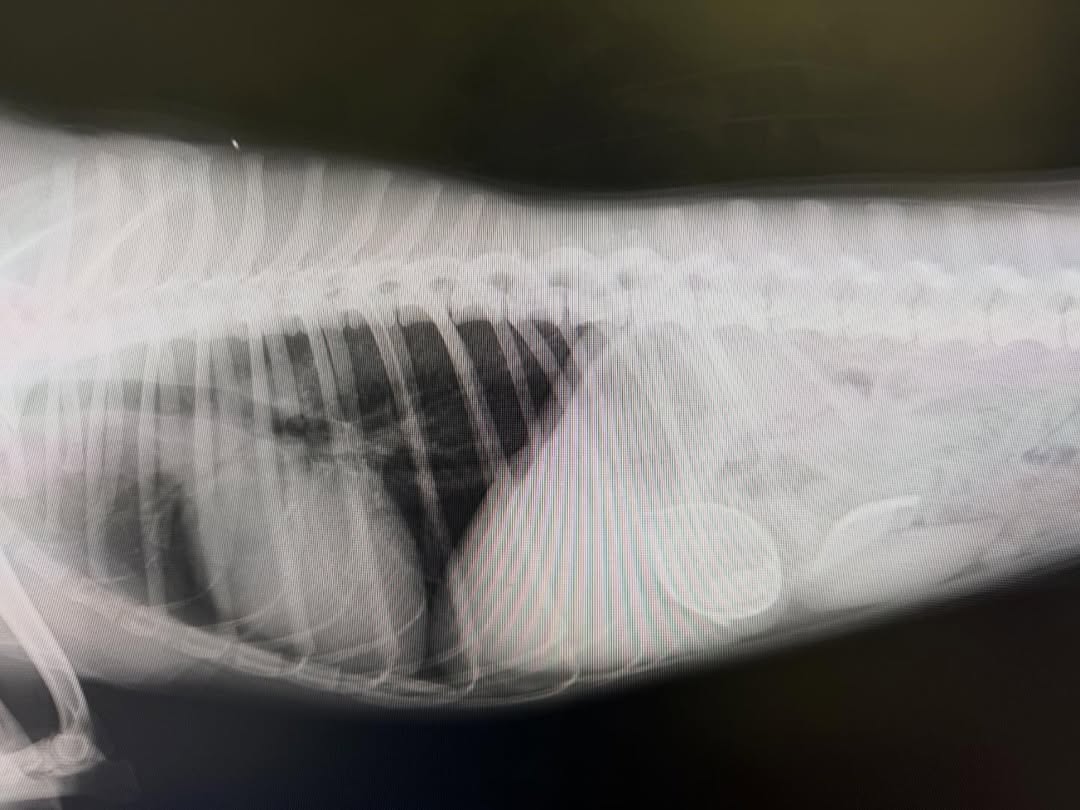

最初の画像の子は、吐くとの主訴で来院され、変なものは食べてないとの事でしたが、レントゲンで明らかに変なものがある。サイズ的にも内視鏡では難しいと判断して本日手術を実施。二枚目の画像のような木の実?のようなものが胃と腸にあり、腸では詰まってました。腸に穴開いたりしなくて良かった。